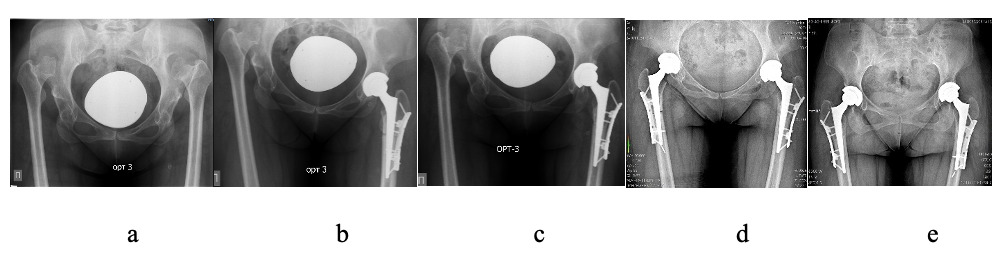

All surgeries were performed between December 2022 and January 2024 by the same experienced surgical team at the Republican Center for Large Joint Arthroplasty. Patients were positioned in the lateral decubitus position. A standard direct lateral (Hardinge) approach was utilized in all cases. Anesthesia was administered as either combined spinal-epidural or general anesthesia, depending on the patient’s preoperative condition and anesthesiologist’s evaluation. Following standard antiseptic preparation, a lateral skin incision approximately 16 cm in length (range, 15–18 cm) was made over the proximal femur. Layered dissection of soft tissues was performed to expose the hip joint. A hypertrophied joint capsule was identified, incised, and partially excised. The femoral head was dislocated, and femoral neck osteotomy was carried out, followed by complete removal of the head. A transverse femoral SSO was then performed approximately 1 cm distal to the lesser trochanter. The true acetabulum was sequentially reamed to the appropriate diameter, most commonly 44 mm. A press-fit, cementless hemispherical acetabular cup was inserted with 95–100% native bone coverage. In cases of deficient bone stock, one or two screws were placed through the cup for supplemental fixation. A polyethylene liner was inserted thereafter. Preparation of the femoral canal was initiated using dedicated rasps, beginning with the distal fragment to facilitate proper alignment of the proximal segment with the true acetabular center. After determining the appropriate implant diameter, the canal was sequentially reamed proximally. The overlapping bone segment was marked, and a second transverse osteotomy was performed to resect 2.5–6.5 cm of bone, based on intraoperative overlap measurement. A conical, cementless modular femoral stem was inserted via press-fit. After trial reduction and intraoperative assessment, patients with axial or rotational instability at the osteotomy site underwent plate osteosynthesis using a derotational plate. The plate was positioned on the lateral surface of the femur and secured using multiple angular stable locking screws in both the proximal and distal fragments to ensure stable fixation. The plate’s geometry provided controlled femoral anteversion and enhanced rotational stability. Final implantation of the femoral stem bridging the osteotomy was performed, followed by modular neck attachment and impaction of a cobalt-chromium femoral head. The femoral head was then reduced into the acetabular liner. The surgical site was irrigated, and wound closure was completed in layers without the use of bone grafts. Final intraoperative radiography confirmed optimal alignment, osteotomy compression, and appropriate implant positioning.

All surgical procedures were performed strictly in accordance with the preoperative plan, without intraoperative deviations. Each patient underwent one-stage total hip arthroplasty (THA) combined with transverse subtrochanteric femoral osteotomy using a standard anterolateral (Harding) approach in the lateral decubitus position. The mean operative time was 101.17 ± 19.68 minutes, and the mean estimated intraoperative blood loss was 424.67 ± 151.95 ml. The osteotomy was performed approximately 1 cm below the lesser trochanter, with a mean resection length of 4.23 ± 1.02 cm, depending on the degree of preoperative limb shortening. In all cases, uncemented conical femoral stems were used. The Wagner Cone implant was applied in 27 cases, while custom-designed conical stems developed at KazNIITO were used in 3 cases. Osteotomy fixation was achieved with a derotational plate designed according to typical femoral morphology based on CT analysis. On average, the plate was secured with 6.4 ± 0.7 locking screws, typically three in the proximal and three in the distal fragment, ensuring axial stability and rotational control. In all patients, the acetabular component was implanted in the true anatomical acetabulum. In 9 cases (30%), supplemental acetabular screws were used to enhance cup stability in the presence of minor superolateral bone deficiency. The mean diameter of the implanted cup was 44.5 ± 2.1 mm, with >90% native bone coverage achieved in all cases. Surgical characteristics and intraoperative implant-related parameters are presented in Table 2.

Radiographic assessment of osteotomy healing was performed at 6 weeks, and at 3, 6, and 12 months postoperatively using standard anteroposterior pelvic radiographs. Healing was classified as complete, partial, or absent. At six weeks postoperatively, no signs of union were observed in 12 cases (40%), while 18 cases (60%) demonstrated early callus formation with incomplete bridging across the osteotomy site (weak consolidation), indicating initial stages of bone healing without full cortical continuity. By the three-month follow-up, complete union had been achieved in 15 cases (50%), with the remaining 15 cases (50%) still showing partial healing. At six months, radiographic examination confirmed complete union in all 30 patients (100%), and this outcome persisted throughout the one-year follow-up period. Statistical analysis revealed that the differences in union rates across follow-up stages were significant (p = 0.006; Friedman test), indicating consistent progression of osteotomy healing. No cases of nonunion, fixation failure, or implant-related complications were observed. These findings highlight the reliability and clinical effectiveness of the derotational plate in providing stable fixation and ensuring complete osteotomy consolidation by six months postoperatively.

Various osteotomy techniques have been described in the literature for managing Crowe type IV DDH, including transverse, oblique, step-cut (Z-shaped), and chevron configurations.19,26,31,37,44 Although complex geometries theoretically offer advantages such as increased bone contact area and enhanced rotational stability, biomechanical and clinical studies have not demonstrated clear superiority over the simple transverse osteotomy in terms of union rates, initial mechanical strength, or clinical outcomes.25,45–47 Due to its technical simplicity, reproducibility, and the ability to achieve precise intraoperative correction of femoral anteversion, the transverse SSO remains the preferred method in most cases.48 In our study, this technique was performed in all patients to allow for safe reduction of the femoral head and correction of excessive anteversion. Stable fixation was achieved using cementless conical femoral stems that bypassed the osteotomy site and provided axial and rotational stability. In all cases, fixation was further reinforced with a custom-designed 3D anatomical derotational plate based on patient-specific CT data. This combination allowed for precise rotational correction and rigid stabilization across the osteotomy, promoting early union and implant stability in the context of complex anatomical deformities encountered in Crowe type IV THA.

According to the data reported by Kawai et al., radiographic union at the osteotomy site was achieved in only 81.5% of patients by 12 months, while 18.5% experienced delayed healing, including one case that required revision surgery with the use of allogeneic strut bone plates.48 In contrast, our series – employing an anatomical derotational plate in conjunction with a cementless conical femoral stem–achieved complete osteotomy union in all patients by the sixth postoperative month, with no cases of fixation failure. These findings highlight the reliability of the proposed fixation construct and its potential to reduce the risk of nonunion in patients with severe hip dysplasia.This is further supported by the radiographic observation that, by one year postoperatively, all implants remained stable with no signs of nonunion. The combined use of an anatomical derotational plate and a cementless conical femoral stem resulted in predictable osteotomy healing and early mechanical stability. Due to its design, the plate provided improved rotational control and additional extramedullary support, effectively addressing the limitations associated with stem-only fixation. In the setting of severe anatomical deformity characteristic of Crowe type IV dysplasia, achieving robust fixation is crucial both for osteotomy healing and for the overall success of THA.37 Although a single intraoperative complication occurred—a proximal femoral fissure during stem insertion in one patient (3.3%)—it was immediately stabilized with cerclage wiring,50 and postoperative recovery was uneventful, with full osteotomy union and no requirement for revision surgery. Importantly, no cases of greater trochanter fracture, gluteus medius detachment, or need for bone grafting, reoperation, or prolonged weight-bearing restrictions were observed. These results reflect both the preservation of abductor integrity achieved through the direct lateral approach and the biomechanical stability afforded by the fixation construct.